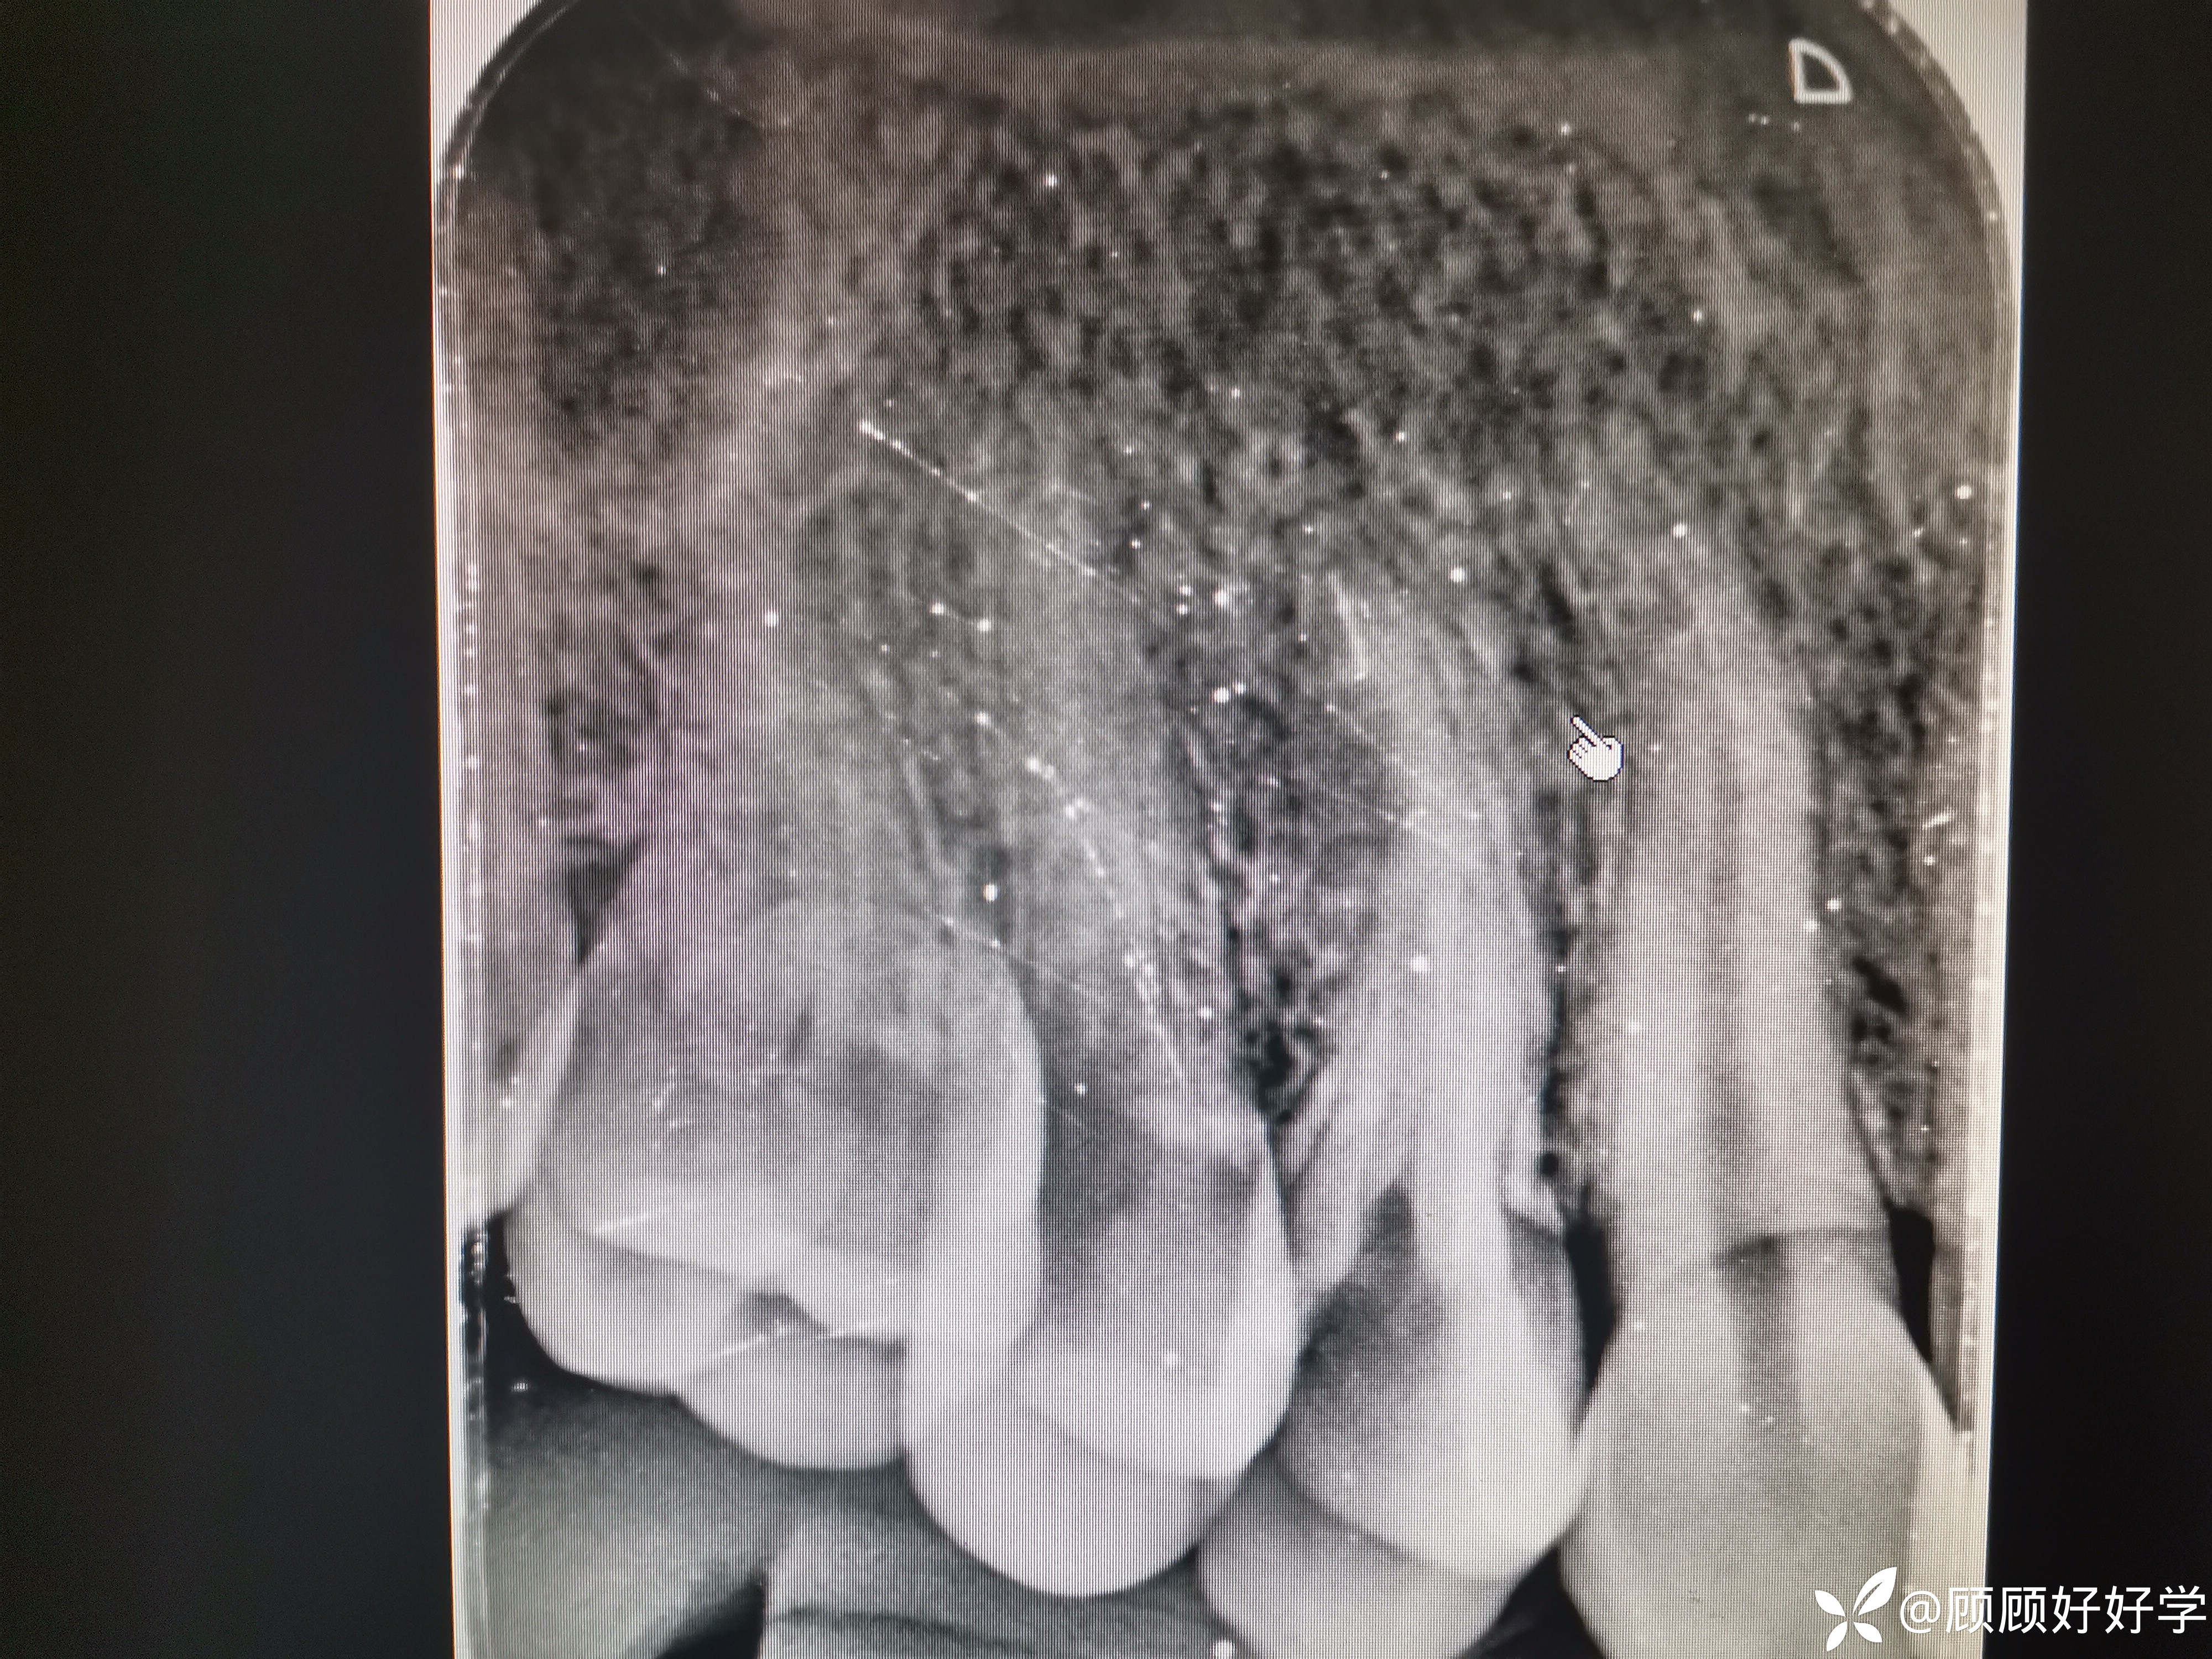

检查:14牙冠远中大面积缺失,窝洞内见粉红色充填物,拍摄根尖片如下